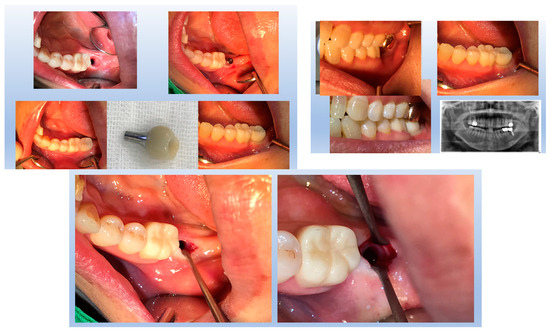

Figure 1 highlights the importance of a carefully designed emergence profile in achieving a natural and biologically stable peri-implant soft tissue interface. In SPI cases, ensuring seamless soft tissue adaptation to implant restoration is critical. By placing coronal flaring submucosally, the transition between the implant and the soft tissue more closely mimics that of natural dentition, enhancing both esthetic and functional outcomes. However, this approach inevitably results in an extended and broader transitional zone within the peri-implant soft tissue.

Figure 1.

The upper first molar was replaced with an implant-supported restoration following the extraction of the natural tooth due to a periapical abscess. The replacement successfully restored both function and esthetics. Notably, attention should be given to the junction between the tooth structure (white) and the soft tissue (pink) in terms of their spatial relationship and proportional dimensions. Although the emerging part of the implant restoration is not externally visible, for a natural appearance, the emergence profile beneath the peri-implant soft tissue must align precisely with the same location and diameter as the cervical area of the neighboring natural teeth. This ensures that the implant restoration maintains continuity with the marginal gingiva at the soft tissue level and the cervical region of the adjacent natural teeth, achieving seamless integration within the oral environment.

For an implant restoration to achieve a natural appearance, the peri-implant soft tissue (pink) and the cervical portion of the implant restoration (white) must be proportional in size and aligned harmoniously with the gingival levels of adjacent teeth. As long as the surrounding gingiva remains healthy, ensuring this precise correspondence from the very first visible point of the restoration supports seamless and natural-looking integration within the oral environment (Figure 1).